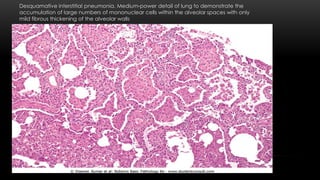

Desquamative interstitial pneumonia. Medium-power detail of lung to demonstrate the

accumulation of large numbers of mononuclear cells within the alveolar spaces with only

mild fibrous thickening of the alveolar walls

Smoking-Related Interstitial Diseases Desquamative interstitialpneumonia (DIP) and respiratory bronchiolitis are the two eg. Accumulation of large numbers of macrophages with abundant cytoplasm containing dusty brown pigment (Smoker's macrophages ) in the airspaces in DIP. - The alveolar septa are thickened by a sparse inflammatory infiltrate (usually lymphocytes), and interstitial fibrosis, when present, is mild. - good prognosis with excellent response to steroid therapy and smoking cessation. Respiratory bronchiolitis . characterized by the presence of pigmented intraluminal macrophages akin to DIP, but in a "bronchiolocentric" distribution (first- and second-order respiratory bronchioles).

Clinical course DIP presents inthe fourth or fifth decade of life, more common males than females 2 : 1. Virtually all patients are cigarette smokers.